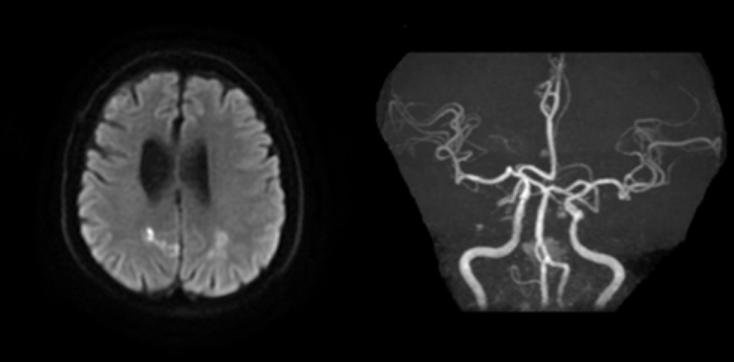

九、脑梗死合并开窗畸形

病例18:左侧扣带回、左枕叶皮层急性脑梗死合并基底动脉起始部开窗畸形

病例19:双侧额顶叶及右侧枕叶多发急性脑梗死合并基底动脉近段开窗畸形